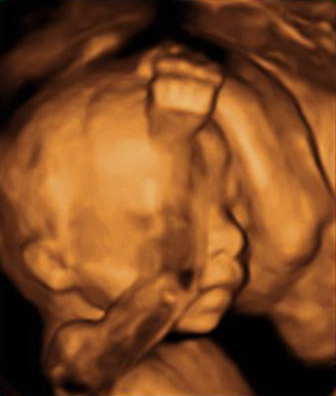

En la semana 20 de gestación, el aparato genital del feto ya es evidente, tanto en niñas como en niños con una ecografía en 4D. Los órganos genitales externos se formaron en la semana 12 de embarazo.

Cómo es el aparato genital femenino del feto en vídeo

En la imagen podemos apreciar un feto del sexo femenino con una edad gestacional de 20 semanas y 3 días.